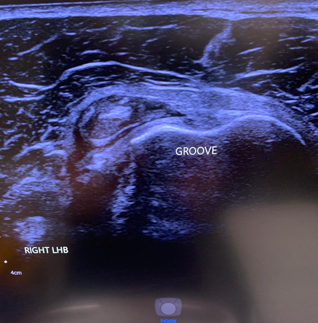

LHB subluxation can happen with contact sports, weight lifting and bodybuilding.

Sometimes the biceps tendon can pop out of its groove. This usually happens because of a tear of the overlying ligament. In other cases, some people are just born with a particularly shallow bicipital groove which puts the tendon at risk of subluxing under load.

Ultrasound findings are of a tendon that is not correctly sited in the bicipital groove (Red circle. The white circle shows where the LHB should sit). To find out more about LHB subluxation: